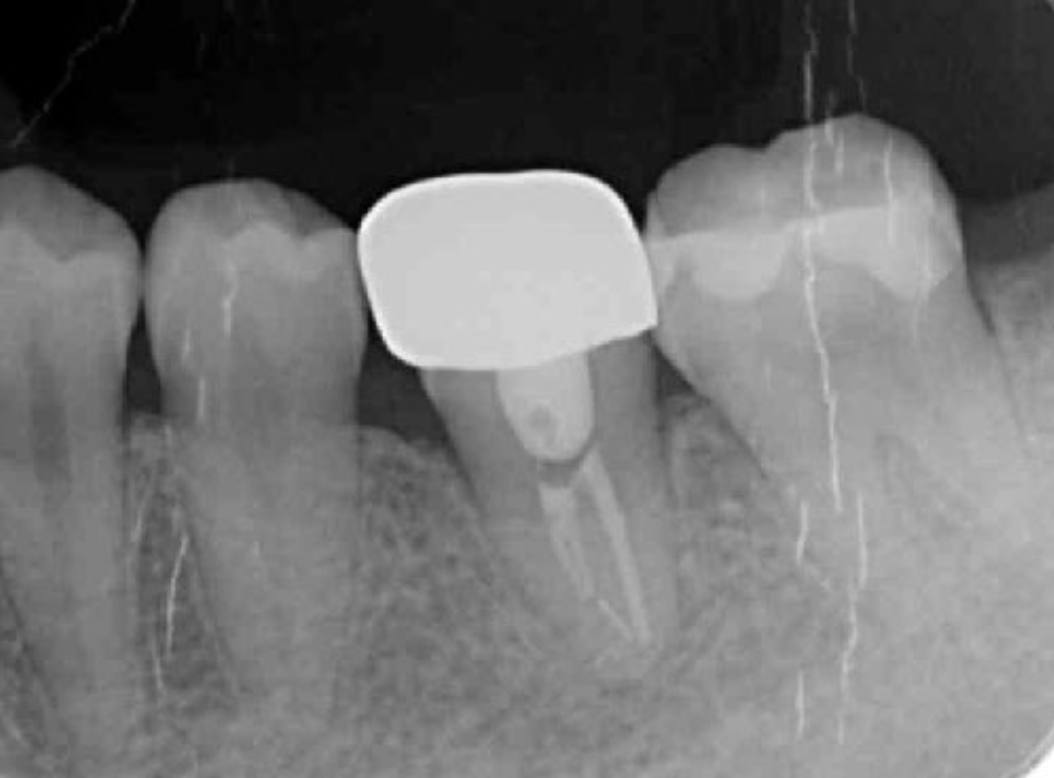

Endodontic treatment was initiated at 14 days after transplantation (8, 17). Root canal treatment for #48 was performed using Ni-Ti files (Pro Taper Next, Dentsply Sirona, Tokyo, Japan) to accommodate the complex morphology of the root canal and for minimal removal of the tooth structure during formation of the access cavity. Root canals were medicated with calcium hydroxide paste and then filled with gutta percha. The splint was also removed four weeks after the operation and a resin core was used as an abutment construction. In an attempt to appropriately modify contact and the crown morphology, a crown prosthesis was made with a full metal crown, with occlusal contact confirmed with use of a temporary crown and easy to visualize markings on occlusal paper. The full metal crown was cemented six months later (Figure 7).

Bone regeneration was confirmed before and after grafting, after root filling, and after placement of the prosthesis, based on X-ray imaging results (Figure 8). There was no pathologic mobility or pain during mastication, and the tooth showed good function. The patient was very satisfied with the treatment results (Figure 9).

Figure 7.Inter-oral photo obtained after treatment. Full metal crowns were inserted for #46, #47. Pathological mobility and bleeding on probing were not seen, and the transplanted tooth showed good function.

Figure 8.Cone beam CT image obtained after transplantation. Bone regeneration around the grafted tooth was confirmed.

Figure 9.Dental X-ray image obtained two years after transplantation. Bone regeneration around the grafted tooth was confirmed.